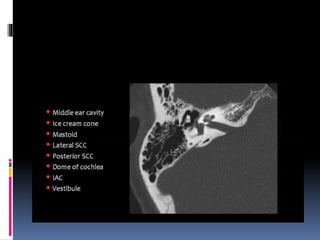

Imaging of the ear

Superior surface of petrous bone

Medial surface of petrous

bone